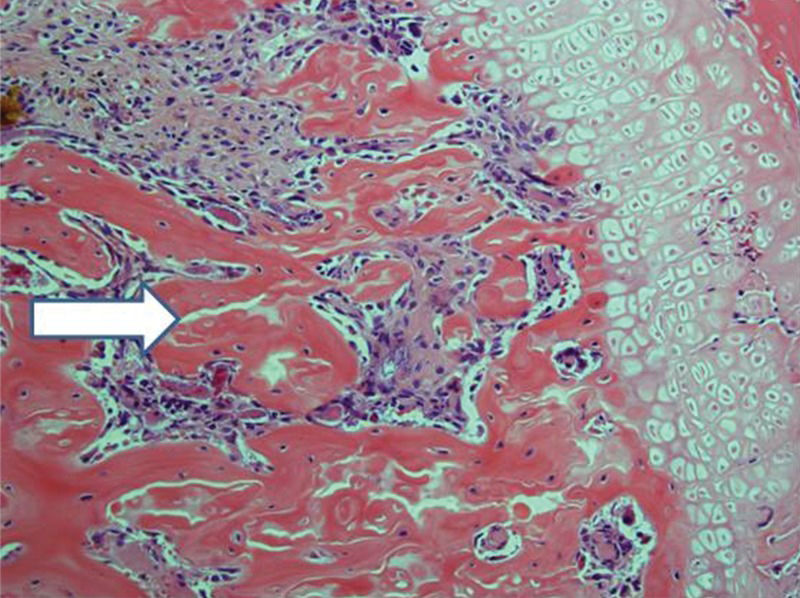

Control femurs exhibited healthy trabeculae and bone marrow histology at all times, as expected (Figure 9). On ischemic slides after 15 days, mild marrow and bone edema could be identified, along with some degree of bone marrow necrosis (Figure 10).

After 30 days, edema was no longer conspicuous. Some areas exhibited bone resorption. The bone marrow did not change substantially compared with that at 15 days (Figure 11). By 60 days, areas exhibiting extensive destruction of the bone and bone marrow could be identified. Nevertheless, as at other time points, the femur showed a generally heterogeneous pattern. Depending on the anatomical location, areas that were in fairly good histological shape were identified, whereas other areas revealed severe damage (Figure 12).